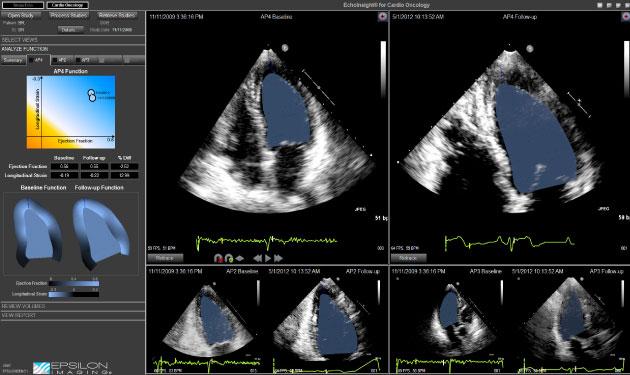

EchoInsight is among the companies pushing for increased usage of strain imaging to improve diagnostic confidence, standardization and efficiency. Epsilon Imaging’s proprietary speckle tracking technology, TissueTrack, provides robust strain imaging with automation of cardiac functional measurements. It provides clinical strain imaging for improved confidence in assessment and monitoring of wall mechanics for the entire heart. It is available as a stand-alone workstation or client-server architecture using a vendor neutral platform.